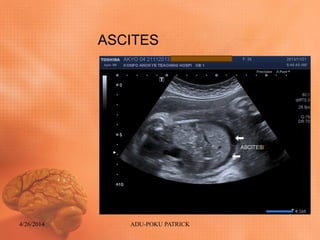

Ultrasound findings: ABDOMEN

• Diffuse skin thickening (Generalized body

Edema)

• Fetal Ascites

• Intact diaphragm

• Normal cord insertion

• Intact stomach

• Hepatomegaly

• Urinary bladder intact

ASCITES